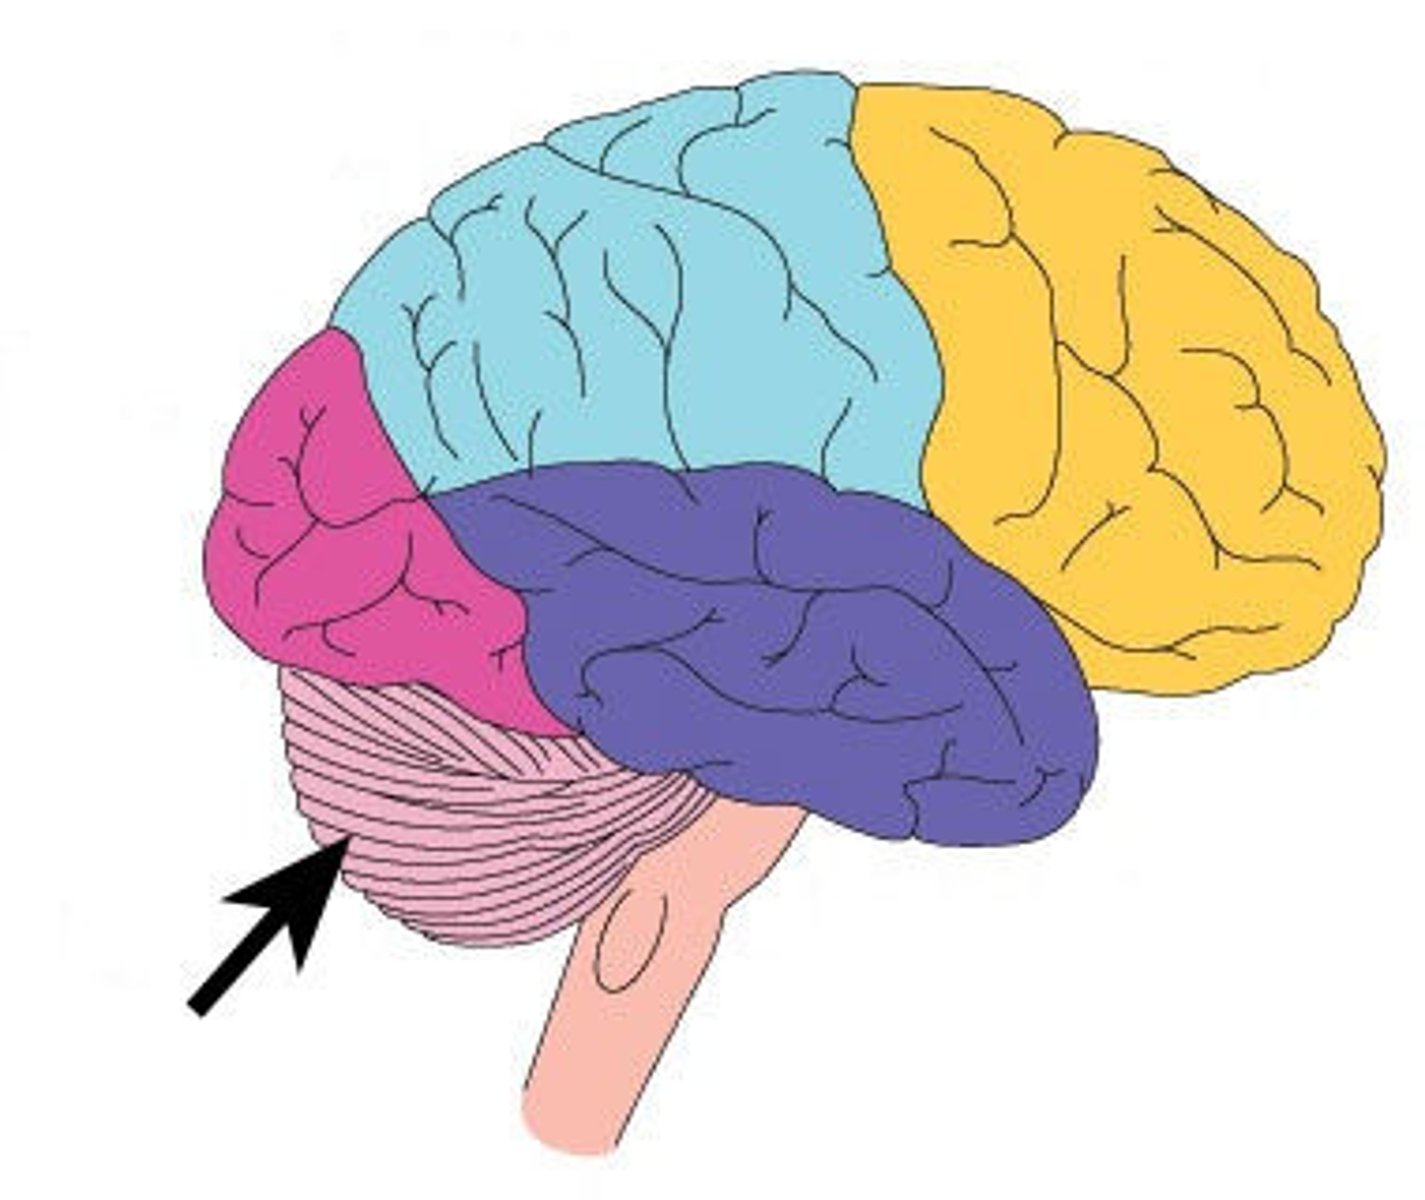

falx cerebelli

seperates the two hemispheres of the cerebellum. it lies inferior to the tentorium cerebelli, separating cerebellar hemispheres (arrow #7)

Cerebellum

posterior part of the brain that coordinates muscle movements and maintains balance